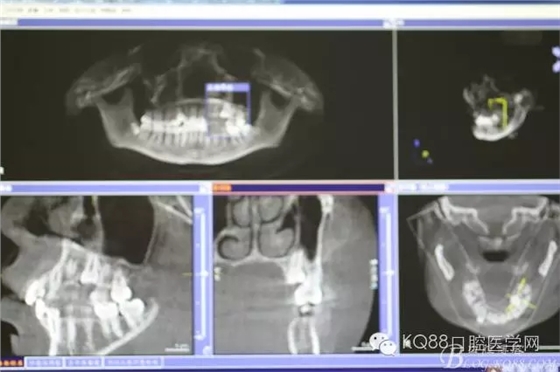

圖3.術(shù)前的CBCT檢查:全景片重建影像,25位于24與26牙根的中1/3處。

圖4.CBCT三維影像顯示:25位于24與26之間的腭側(cè)